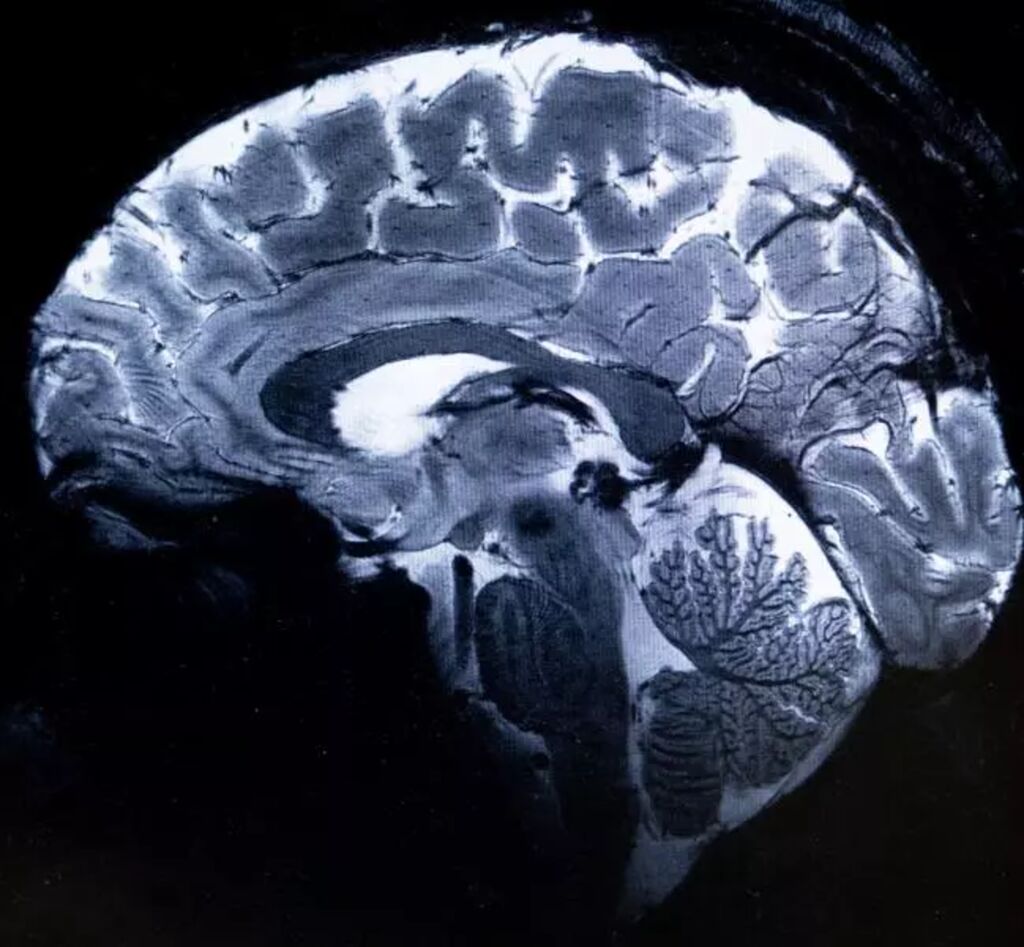

| Cette image réalisée avec l'IRM Iseult montre un cerveau lors d'une simulation d'examen d'imagerie par résonance magnétique (IRM), au centre du Commissariat à l'énergie atomique et aux énergies alternatives (CEA) de Paris-Saclay à Gif-sur-Yvette, le 22 mars. |

Le champ magnétique de cet aimant hors norme atteint 11,7 T (tesla), permettant l'obtention d'images 10 fois plus précises que celles produites actuellement dans les hôpitaux, où la puissance des IRM ne dépasse pas 3 tesla.

Sur l'écran d'Alexandre Vignaud, des images de coupes de cerveau sont comparées avec ce qu'aurait donné un IRM de 3 ou 7 tesla : "Avec cette machine, on peut voir les tout petits vaisseaux qui alimentent le cortex cérébral ou des détails du cervelet qui étaient quasi invisibles jusqu'alors", commente-t-il.